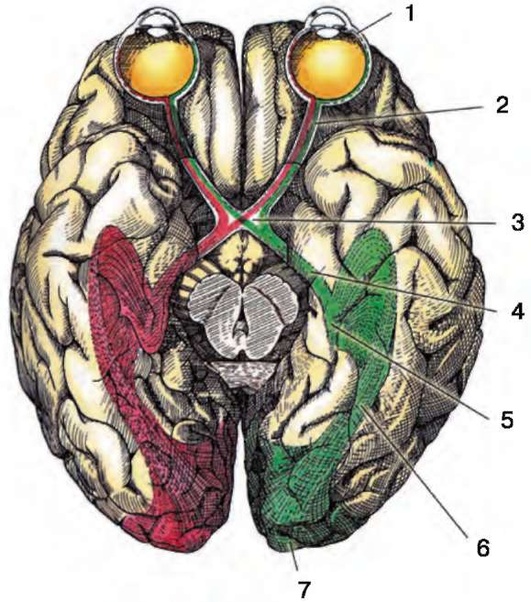

Рис. 2.1. Путь зрительных импульсов: 1 - глаз; 2 - зрительный нерв; 3 - неполный перекрест зрительных нервов (хиазма); 4 - зрительный тракт; 5 - наружное коленчатое тело; 6 - зрительная лучистость; 7 - первичная зрительная кора